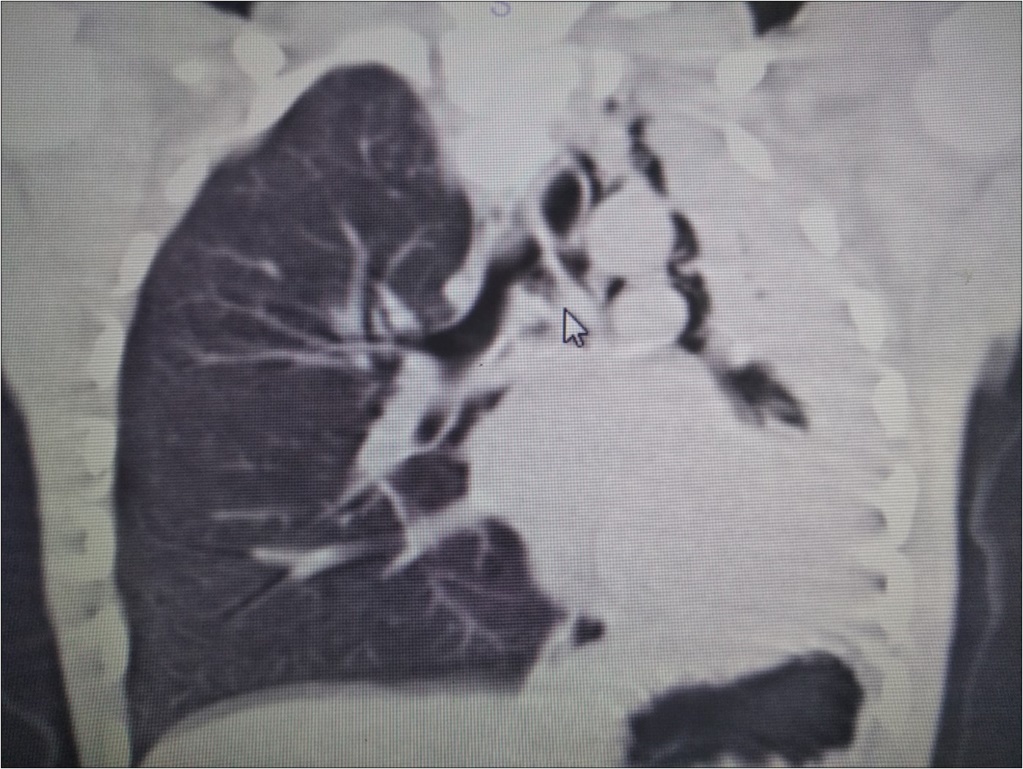

A 6 year-old boy was admitted to our hospital with the symptoms of upper respiratory tract infection (URI). He had hemoptysis 2 days prior to admission to hospital. On admission he had respiratory distress, fever (39°). Plain chest graphy demonstrated a complete opacification of the left lung (Figure 1). Thorax ultrasonography was normal and high resolution computed tomography (HRCT) of the chest revealed a 50-60% narrowing of the left main stem bronchus starting from carina downwards (Figure 2). Although there was no history of foreign object aspiration an emergent bronchoscopy was performed for a possible unnoticed aspirated foreign body. A bronchial cast located at the carineal bifurcation of trachea measuring 3x1 cm was detected and easily removed with forceps during bronchoscopy (Figure 3). The material was whitish, rubbery in consistency. Histopathologic examination of the cast revealed that it consisted of condensed fibrin, neutrophils and eosinophils. Culture was also obtained from the specimen for a possible bacterial growth. Following bronchoscopy the patient required mechanical ventilation for ventilatory support in the mode of high frequency oscillatory ventilation (HFOV) with supplementery oxygen in intensive care unit (ICU). In his 3rd hospital day, control chest graphy of the child showed complete opacification of the left lung and for a chance of residual cast in the tracheobroncial tree a repeat bronchoscopy was performed. Two seperate casts from the left main stem bronchus measuring 1.5x1 cm and 2x1 cm in length were removed with forceps and lavage with aspiration of both right and left main stem bronchus was performed. Following second bronchoscopy the transcutaneous oxygen saturation increased from 77 to 99 and control chest roentgenogram showed equal expension of both lungs. While in his stay in ICU, in addition to mediacal treatment, respiratory physiotherapy was performed regularly. He was medically treated with aerosolized dexamethasone with adrenalin. Bacterial test obtained from cast was found positive for Streptococcus viridans and vancomycin was started. On his 5th day in ICU, his respiratory status worsened and a chest graphy showed a decrease in expension of the left lung and a control bronchoscopy was performed. In this third bronchoscopy trachea and both right and left main stem bronchus were found to be patent but were found to have excessive viscous secretions. Pulmonary toilet including lavage and aspiration of thick tenacious secretions was performed. On day 12 he was transferred from the ICU and 1 week later he was weaned off the ventilator. He underwent pulmonary rehabilitation. During his 3rd year of follow up he has no further episodes of respiratory distress and he is disease free.

Figure 2.HRCT of the patient showing narrowing of the left main stem bronchus starting from carina downwards.

Radiographic findings are nonspecific and include atelectasis secondary to airway obstruction, hyperinflation due to air trapping, unilateral opacification, as seen in our case, bronchiectasis and lung infiltrates. It has been reported that HRCT may allow in some cases the visualization of bronchial casts in the airways of larger caliber 19. However the gold standard in diagnosing PB is bronchoscopy which reveals the airway obstruction by BC 3.